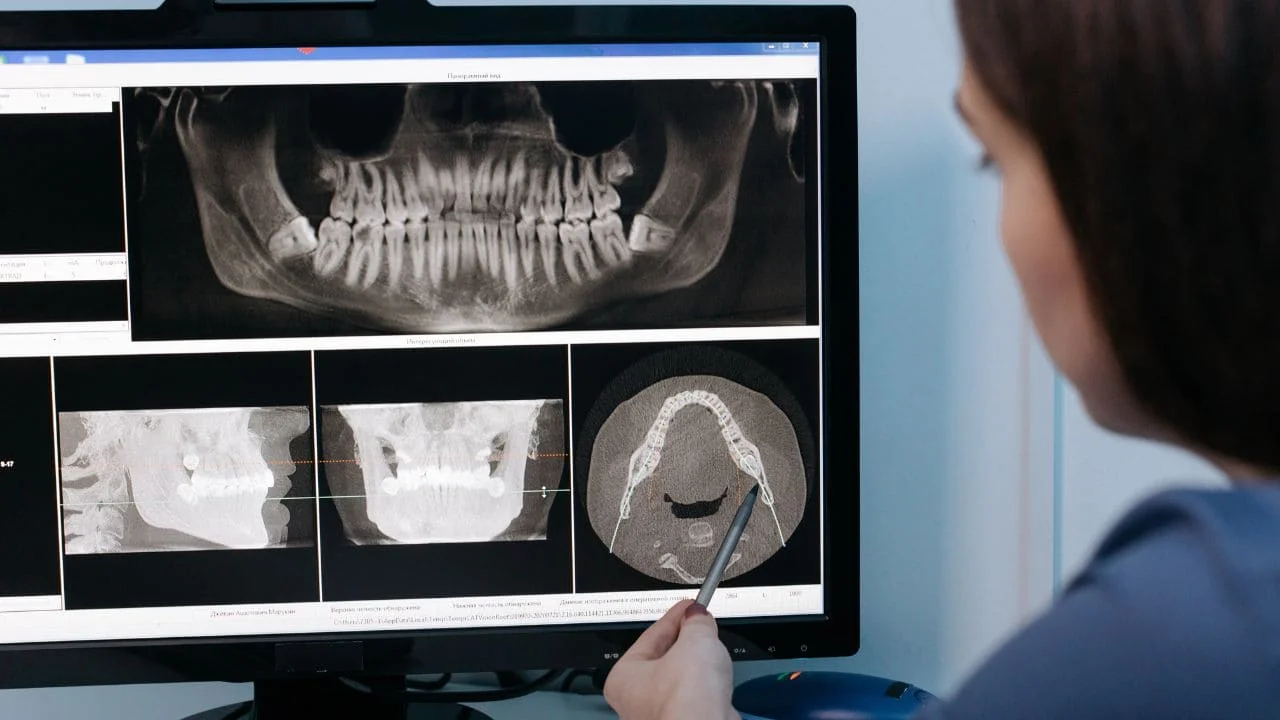

3. Radiographie (si nécessaire) : Une radiographie peut être prise pour s’assurer qu’aucun fragment osseux ou dentaire n’est resté en place et pour évaluer l’état de l’os sous-jacent.